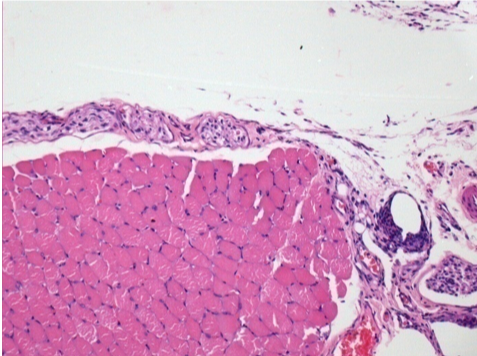

10 giorni dopo iniezione di Endopeel

Scatola Nr 2

- 10 giorni dopo iniezione 0.1ml di Endopeel nel muscolo pretibiale destro (Dx).

- Si osserva formazioni di vacuole , le quali circondate da linfociti.

- Le quali Vacuole sono differenti dal tessuto necrotico.

- La presenza di linfociti é correlata alla permeabilità delle membrane cellulari.

Sx : Controllo-100x-Giorno10

Dx:100x-Giorno10

Dx :200x-Giorno10

Dx :400x - Giorno10